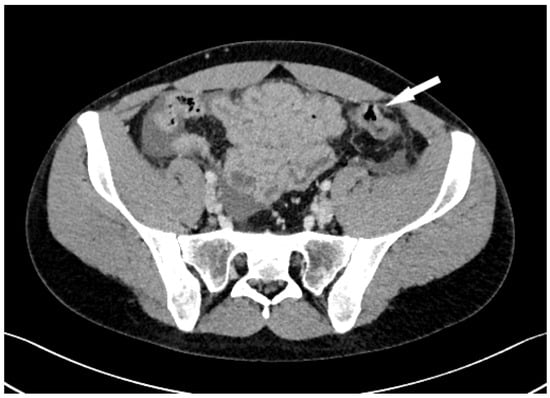

A 23-year-old male was admitted to the Emergency Department at University Hospital Centre Zagreb because of a sudden, cramp-like pain radiating from the back to the left inguinal region that started 20 min prior, without nausea, vomiting, or fever. Physical examination showed the abdomen at chest level, diffusely painful on palpation, with peritoneal irritation and muscle defense. Admission laboratory findings were as follows: erythrocytes 5.13 × 1012/L, hemoglobin 147 g/L, hematocrit 0.436 L/L, MCV 85 fL, thrombocytes 302 × 109/L, leukocytes 17.5 × 109/L, bilirubin 5 µmol/L, urea 3.4 mmol/L, creatinine 77 µmol/L, ALP 81 U/L, ALT 71 U/L, GGT 26 U/L, glucose 8.4 mmol/L, potassium 3.4 mmol/L, natrium 140 mmol/L, calcium 2.26 mmol/L, CRP < 1 mg/L, and GF-CDK 122 mL/min/1.73 m2. The electrocardiogram was normal, with a heart rate of 110 bpm. A plain abdominal X-ray was normal. Abdominal CT showed pneumoperitoneum with a large amount of fluid in the pelvis and abdomen, indicating hollow viscus rupture (Figure 1). At the transition to the sigmoid colon, a defect in the intestinal wall and gas bubbles were seen. The appendix was 1 cm long, without visible signs of acute appendicitis. The morphology of the abdominal parenchymal organs was normal. The biliary and urinary tract systems were not dilated. Bullous changes in the lung parenchyma were seen at the bases. Medical history revealed right-sided pneumothorax at the age of 15 and left-sided at 16 (both required VATS bullectomy), as well as bilateral inguinal hernia repair at the age of 3. The patient received 1 amp of trospium chloride, 1 amp of metoclopramide, and 100 mcg iv. fentanyl in the emergency department. The working diagnosis was an acute abdomen from the sigmoid colon perforation of unknown cause. Emergent median laparotomy showed abundant intestinal contents in all quadrants. After extensive lavage, sigmoid colon perforation was confirmed, and a loop sigmoid colostomy at the perforation site was made. On the sixth postoperative day, the patient became febrile, and CRP values increased. Abdominal CT showed a large amount of intraabdominal free fluid with small-bowel distension and air-liquid levels, so reoperation was indicated. At relaparotomy, distended small-bowel loops were found in the left lower quadrant, which had abundant clear free fluid. The appendix looked macroscopically changed, probably secondary. Lavage, appendectomy, and terminal ileum resection with end ileostomy were conducted. Interestingly, ileal subserosal hematomas (Figure 2) were found. Many of these ruptured, leaving a “zebra pattern” with lines of residual hematomas on the borders of subserosal hematomas (Figure 3).

Figure 1.

Abdominal CT shows sigmoid colon perforation (arrow).